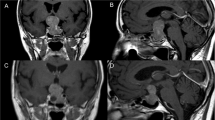

Heteroplasmy occurred in 482 of the detected 496 variants at least in one sample and overall on low level (indicated by colours on cluster heatmap, Fig. 1a). Hormone-immunonegative (HN) adenomas showed a slightly higher heteroplasmy prevalence compared to GO and GH adenomas 8.27% vs. 6.96 and 6.72%, respectively (Table 2). This remained the same after dissection of protein-coding and non-coding variants (Table 2). In addition, we did not find difference in Ki-67 proliferation index or tumor size between sample groups harbouring low (< 50%) and high (> 50%) heteroplasmy.

Possible associations with clinicopathological features. a Profile of detected variants showed overall low level of heteroplasmy and hierarchical cluster analysis could not discriminate pituitary adenoma samples based on either histological type, Ki-67 index, or recurrent/non-recurrent status. The colour scale indicates the ratio of heteroplasmy obtained by NGS, where 0 (blue) shows 100% reference allele and 1 (green) shows 100% variant allele. b Number of the found variants in pituitary adenoma samples, grouped by histological type and ranked from fewer to more variants. Analysing the samples harbouring the highest number of variants obtained that they have the highest Ki-67 indices independently of histological type. c Regarding the number of the variants, we identified 143, 58, and 52 unique variants appeared only in GO, HN, and GH-secreting adenomas, respectively. Legends: rec: recurrent, non-rec: non-recurrent, Ki-67 group 1: Ki-67 proliferation index is between 1 and 4%, Ki-67 group 2: Ki-67 proliferation index is between 5 and 10%, Hist histological subtype, GH growth hormone producing, GO gonadotroph, HN hormone immunonegative

On average, 35 variants were detected per sample. Similar results were obtained in different histological groups: we found 33, 34 and 40 variants per sample in GH-producing, gonadotroph, and hormone-immunonegative adenomas, respectively. Furthermore, samples harbouring the highest number of variants (Fig. 1b) had the highest Ki-67 indices [Ki-67: 8% (GH), 7–10% (GO), and 5% (HN)] independently of histological type.

When analysing distinct histological groups, we identified 143, 58, and 52 unique variants that appeared only in GO, HN, and GH-secreting adenomas, respectively (Fig. 1c, Online Resource 2).

Using hierarchical cluster analysis on all variants, no clear separation of the samples was identified based on histological type, Ki-67 index, or recurrent/non-recurrent status (Fig. 1a).